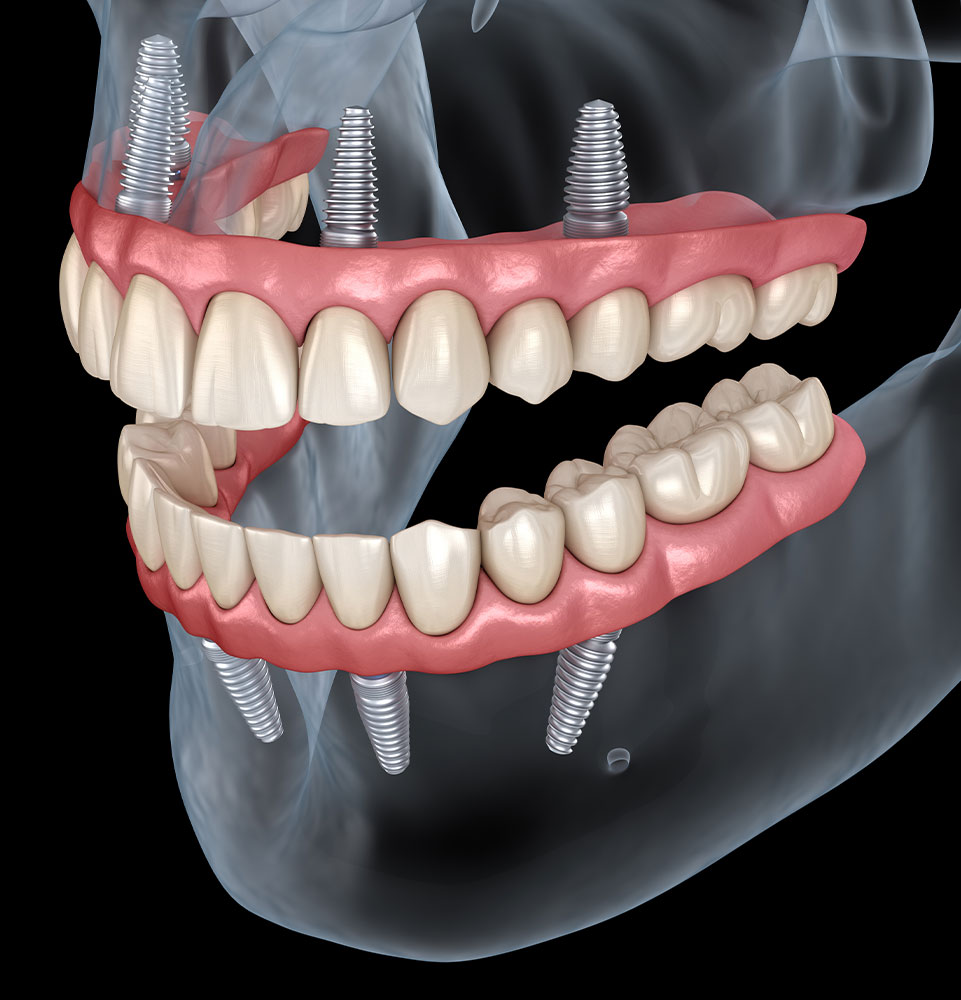

Richardson Family & Implant Dentistry offers complete dental care, from cleanings to implants and cosmetic treatments, in a comfortable setting.

Richardson Family & Implant Dentistry (Formerly Kelly Halverson, DDS, FAGD), located in the heart of Richardson, Texas, offers comprehensive dental care and oral health solutions. Our experienced team will provide you with a warm and exceptional experience. From routine checkups and cleanings to cosmetic dentistry, teeth whitening, and emergency services, we have everything covered.